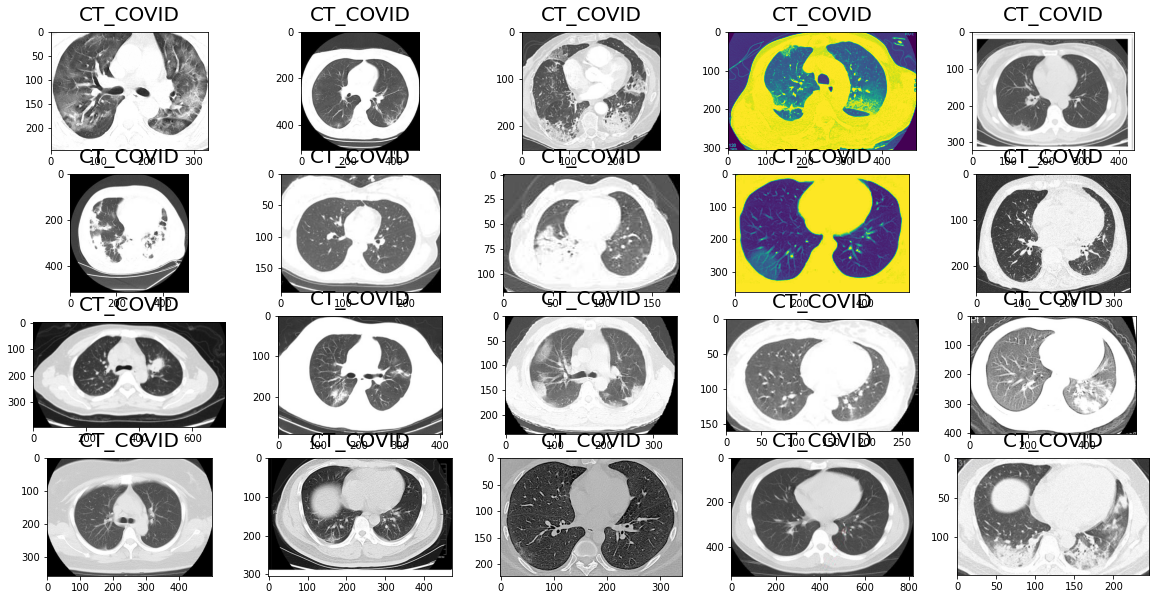

2.2 查看CT_COVID(阳性) 阳性数据集

dataset='./Images-processed/'

ct_h = os.path.join(dataset,"CT_COVID")

select_ct="CT_COVID"

rows,columns = 4,5

display_folder=os.path.join(ct_h,select_ct)

lists = os.listdir(display_folder)

# print(lists)

lists = enumerate(lists)

print(lists)

total_images=rows*columns

fig=plt.figure(1, figsize=(20, 10))

for i, j in lists:

img = plt.imread(os.path.join('./Images-processed/CT_COVID/CT_COVID/',j))

fig=plt.subplot(rows, columns, i+1)

fig.set_title(select_ct, pad = 11, size=20)

plt.imshow(img)

if i==total_images-1:

break